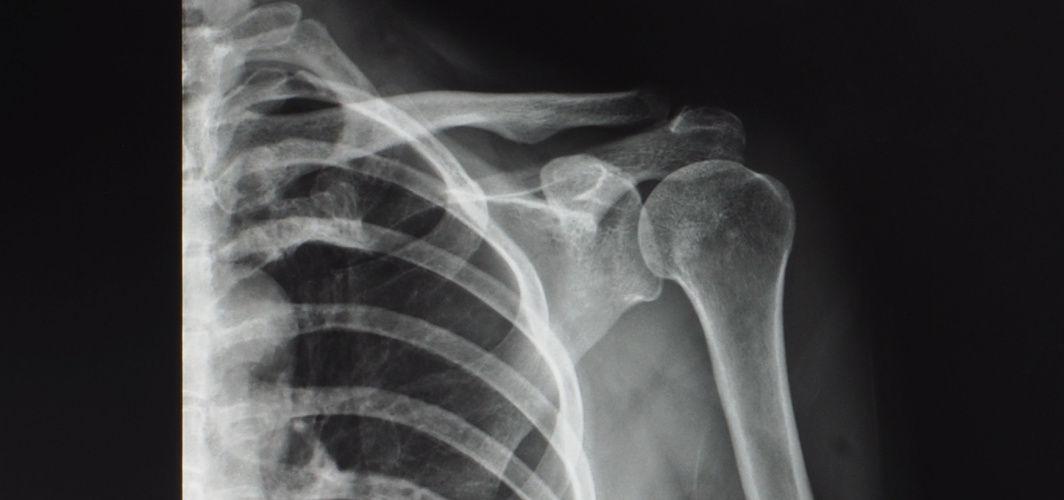

Did you know, the word arthritis is derived from the Greek word “arthron”, which means joints, while “itis” means inflammation. Arthritis is an inflammatory condition that can affect anyone but is more prominently seen in women. Research shows that more than 500 million people suffer from arthritis globally. While the disease is very common, the cure has not been fully understood yet. Let us understand more about the causes of arthritis and the ways to manage it.

Arthritis is a disabling disease that can cause swelling, chronic pain, stiffness and reduced range of motion in the joints, which can make it difficult to even walk or climb stairs. While the symptoms may not progress immediately, they can get worse over time. There is no cure for arthritis, however, if diagnosed accurately it can be managed with exercise, hot and cold compression, assistive devices, and relaxation therapies. People experiencing signs of arthritis must consult a bone specialist (orthopaedic doctor) for further investigation.